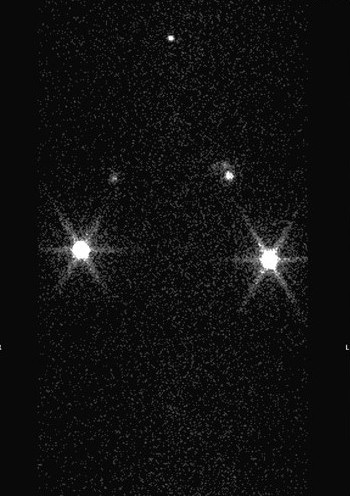

lymphoscintigraphy

SPECT CT

SPECT/CT Lymphoscintigraphy:  SPECT/CT stands for single-photon-emission computed tomography. This scan consists of combining a CT scan (which lets us see your anatomy clearly) with a scan that tracks the progression of a tracer through that anatomy over a certain period of time. It lets us see the volunteer's anatomy with clarity as the tracer moves through.